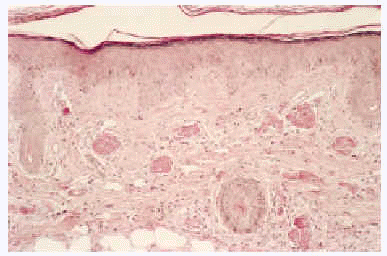

Desde el punto de vista anatomopatológico podemos encontrar hallazgos histológicos típicos de vasculitis leucocitoclástica o signos de poliarteritis nudosa (PAN). El momento más adecuado para realizar la biopsia es a las 24 a 48 horas de la aparición de las lesiones. En la vasculitis leucocitoclástica hay afectación de vaso pequeño (arteriolas, vénulas y capilares) y la arquitectura vascular está alterada por un infiltrado inflamatorio mixto que rodea los vasos e incluso penetra en ellos (fig. 4). Las células endoteliales se muestran prominentes y la presencia de leucocitoclasia y extravasación hemática puede completar el cuadro. Debemos recordar que la leucocitoclasia es un dato no específico, que simplemente revela un infiltrado neutrofílico importante y puede verse en otras entidades como el síndrome de Sweet o diversas infecciones cutáneas. La PAN afecta vasos medianos y pequeños, con presencia de necrosis fibrinoide y un infiltrado inflamatorio mixto de monocitos, linfocitos y polimorfonucleares neutrófilos que interrumpen y borran la arquitectura vascular (fig. 5)19. La presencia de trombos de aspecto hialino, eosinófilos, PAS positivos, ocluyendo la luz de los vasos, aunque muy típica, no es muy frecuente salvo en la CGM tipo I (fig. 6), en la que coinciden con criocritos muy elevados, mientras que las alteraciones de vasculitis, especialmente en las CGM tipo II, son más frecuentes con criocritos bajos. Este fenómeno continúa aún sin explicación, aunque parece deberse a la capacidad intrínseca de los inmunocomplejos de activar el complemento in situ.

Fig. 4.--Típicos hallazgos histológicos de vasculitis leucocitoclástica.